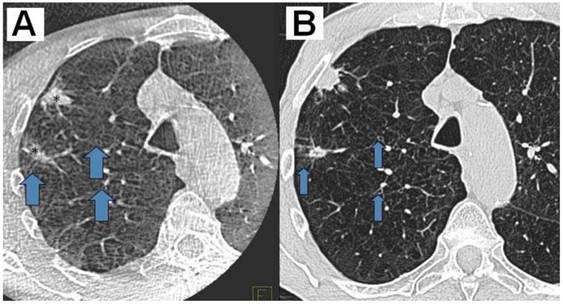

Figure 1

A) DynaCT with a bit of motion artefact, B) Right: HRCT 1mm nearly same level; slices same patient (2 adeno-carcinomas: *) Showing the same nice details (arrows at the same position indication bronchioli of 2mm and less).